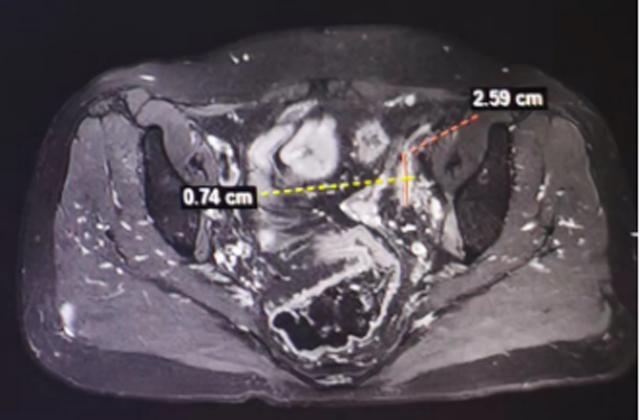

入组前病灶大小

近期疗效评估病灶大小(部分层面代表)